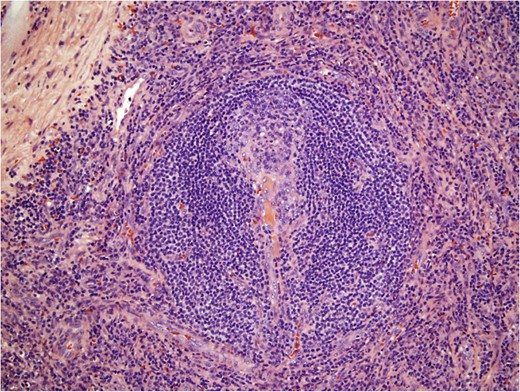

Histological examination (Fig. 3) diagnosed an accessory spleen with unicentric Castleman’s disease (UCD) hyaline vascular variant (7.7 × 6.0 × 5.8 cm3) without pathologic changes to the attached lymph node (2.2 × 2.3 × 2.0 cm3) or the encased adrenal gland (5.5 × 1.5 × 0.8 cm3). A blood panel revealed no evidence of leukemia or lymphoma. The patient was seen for follow-up 1 week postsurgery and reported no pain or discomfort. She will continue to be monitored with physical examinations, scans and serum tumor markers.

Histological pathology of Castleman’s disease, hyaline vascular variant. Involuted follicular germinal center penetrated by hyalinized small vessels and surrounded by concentric ‘onion rings’ of mantle zone lymphocytes.